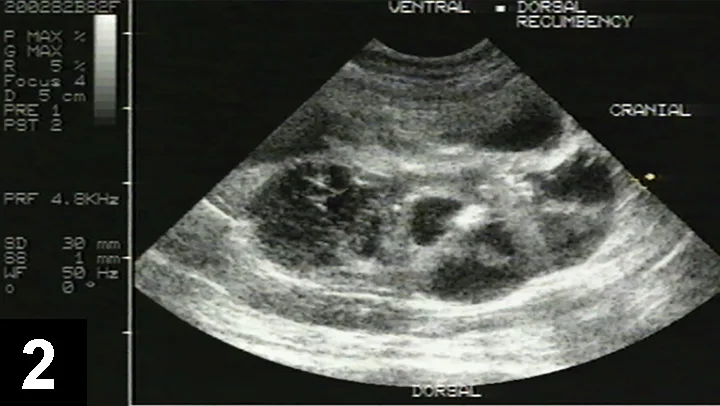

Gross pathology image of 2 kidney sections showing parenchyma nearly completely obliterated by cysts.

FIGURE 1

Necropsy of both sectioned kidneys from a cat with PKD; note fluid-filled cysts of varying sizes and obliteration of large portions of both the cortex and medulla. Only scant amount of renal parenchyma (pink) remains. Image courtesy of Dr. Susan Little.

• PKD progresses slowly as portions of the cortex and medulla are replaced by cysts (Figure 1).